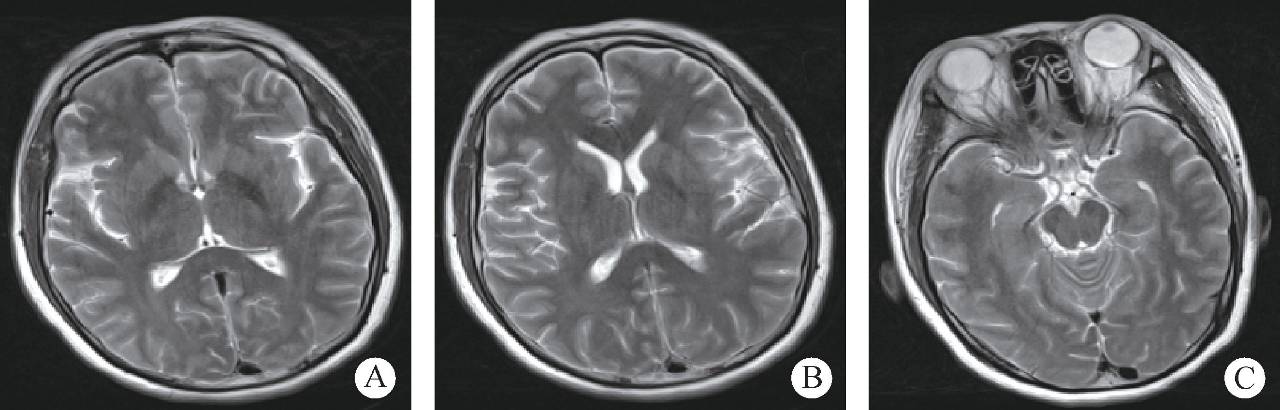

患者女性,36岁,经阴道自然分娩2天后,突发喷射样呕吐,伴有头晕、视物不清及意识障碍,随后出现胡言乱语、答非所问。发病3小时后出现呼之不应、牙关紧闭、四肢乱动、双眼直视、伴舌咬伤,入院后查体见球结膜出血水肿,颜面部出血伴皮下出血点,对光反射迟钝,疼痛刺激反应正常,无其他阳性体征,监测生命体征,完善各项影像学检查均未见明显异常(图1、图2)。

图2 头颅MRI+MRA+MRV (未见明显异常)

妊娠期水中毒的诊断主要依靠临床表现及实验室检查,影像学常无特异性表现。MRI成像对于水中毒脑组织受损情况具有一定的诊断价值。轻度水中毒患者MRI成像可能无明显异常表现,典型患者可表现为脑实质T2WI信号增高、缺血脑组织DWI高信号等特征。此外可以应用TCD观察水中毒患者脑CBF及脑血流动力学的改变。同时,也可以应用MR灌注成像观察水中毒患者的脑血流灌注情况。(点评专家:高晓娟,首都医科大学附属北京天坛医院妇产科)